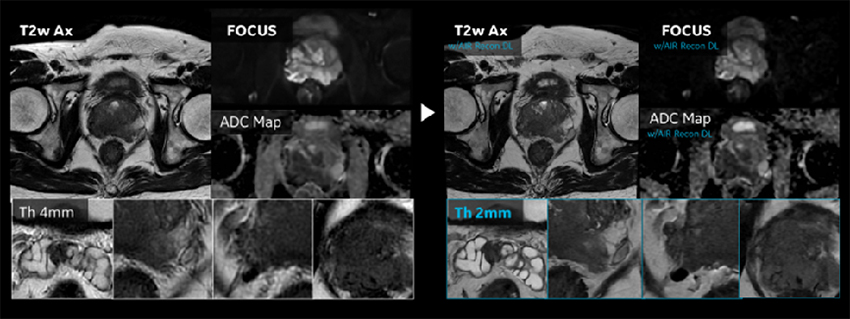

2-3. 前立腺

前立腺はAIR™ Recon DLの機能が最も効果的に活用されている領域の一つで、「SNR向上」「Thin slice化」「撮像時間短縮」の3つの恩恵が効率的に得られている。特に前立腺MR診断における重要なコントラストであるT2強調像と拡散強調像の画質向上効果の恩恵が大きい。

従来の前立腺のT2強調像プロトコルは、PI-RADSに準拠してスライス厚3mmで行っていたが、AIR Recon DLの導入により2mmで行っている。従来のシステムでPI-RADSに準拠したプロトコルを設定した場合、十分なSNRを得るためには時間をかけて撮像を行う必要があったが、AIR™ Recon DL導入システムでは2mmで撮像を行ってもSNRが十分に保たれた画像を、2分台で得ることが出来る(Figure.3)。部分容積効果の低減により前立腺のコントラストが明瞭になり、淡い信号領域内の低信号域が検出され、臨床的価値の高い画像が提供される。さらに前立腺がんの被膜外進展の検出にも有効で、脂肪織への浸潤などの同定に有用である。AIR™ IQ Editionによる画質向上によって微細な構造が見えるようになり、診断の信頼性が向上していると感じている。

Pironeer_Kosugi_05.jpgFigure. 3

前立腺プロトコルの変遷。従来より薄いスライスで撮像することにより部分容積効果を低減させて、シャープな画像を得ることが出来る。